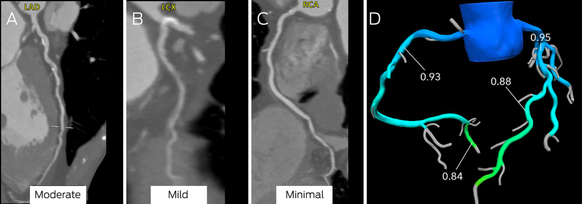

Box 9 – Computed tomography coronary angiography (CTCA) images (A–C) and computed tomography‐derived fractional flow reserve (CT‐FFR) assessment of stenosis (D)*

LAD = left anterior descending artery; LCX = left circumflex; RCA = right coronary artery.

Moderate stenosis is evident in the mid‐left anterior descending coronary artery (A), mild disease in the left circumflex coronary artery (B), and minimal disease in the right coronary artery (C). There was no evidence of ischaemia in the left anterior descending coronary artery (D; CT‐FFR, 0.88; normal > 0.80).